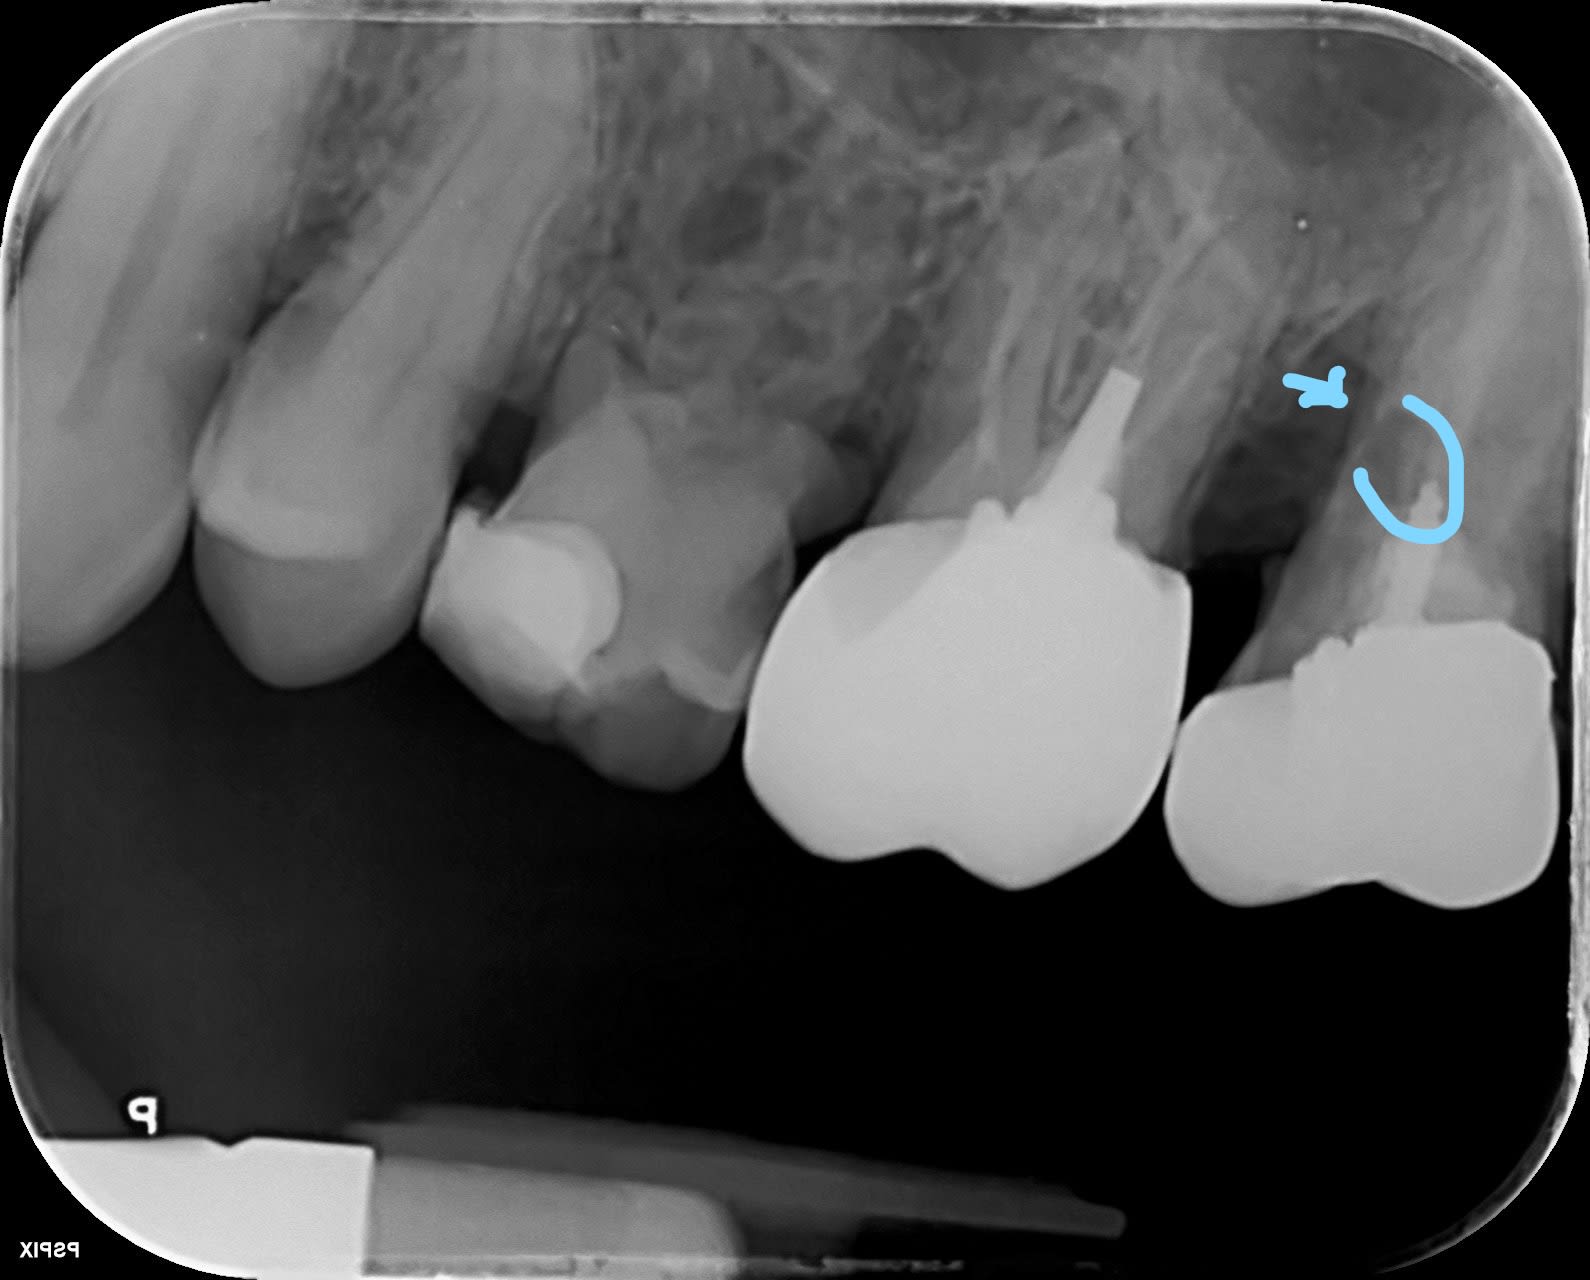

Et celle-ci tu ferais quoi pour la 6 ? :) retraitement ou extraction ?

Tout d'abord hemisection de la racine mésiale de la 6 et traction orthodontique de la 5 avec une potence fixée à la 6.

Ensuite reprise endo de la 6 et la 5.

Ensuite ERI de la 5 et/ou de la 6 si échec du retraitement.

Ensuite I core sur 5 et 6 et pour finir 2 coiffes solidarisees.

J'ai bon ?

Je vire les deux et je cloue.

Ah c’est le Vulpi qui a bon :) photo avant extraction et EII